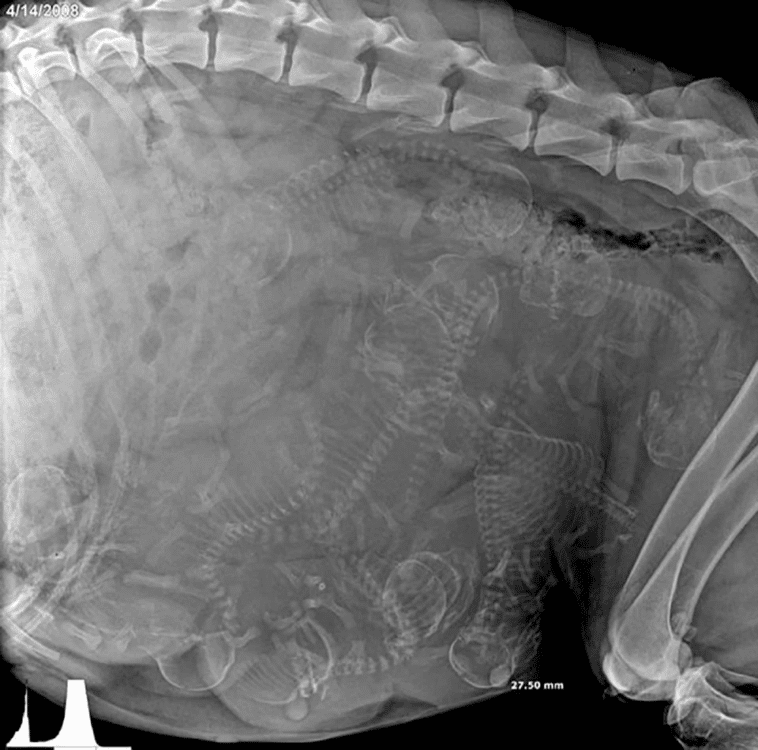

in Fotos, Imagenes interesantes Radiografía de una perra preñada What do you think? 0 Points Upvote Downvote Leave a ReplyYour email address will not be published. Required fields are marked *Comment * Name * Email * Website Save my name, email, and website in this browser for the next time I comment.